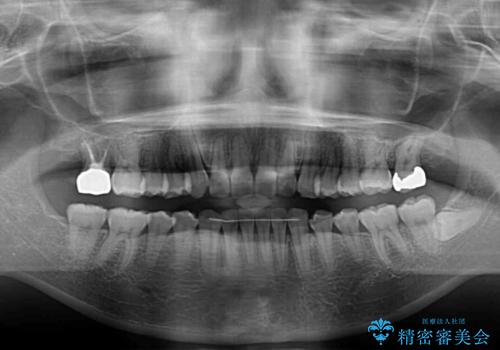

- 奥歯の咬み合わせと治療を放置したまま奥歯を気にして来院された患者様です。

上顎骨の幅が下顎骨よりも小さいので、拡大装置により骨幅を広げて上下関係を改善し、その後インビザラインにて歯並びを整えることとしました。

矯正治療後には土台のままとなっている歯をセラミッククラウンにて補綴治療を行うこととしました。

上下の骨幅を改善したことで、スムーズに歯列矯正を行うことができました。

土台のまま放置されていた歯は土台の状態で咬み合っていましたが、急速拡大を行った際に咬み合わせが著しく挙上されたため、その際に土台を大きくすることで咬み合う歯との距離を確保しました。